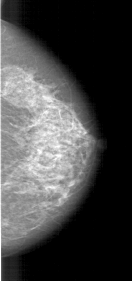

A_1461_1.LEFT_MLO

LEFT_CC LINES 6856 PIXELS_PER_LINE 2851 BITS_PER_PIXEL 12 RESOLUTION 43.5 OVERLAY

LEFT_MLO LINES 6871 PIXELS_PER_LINE 3241 BITS_PER_PIXEL 12 RESOLUTION 43.5 OVERLAY